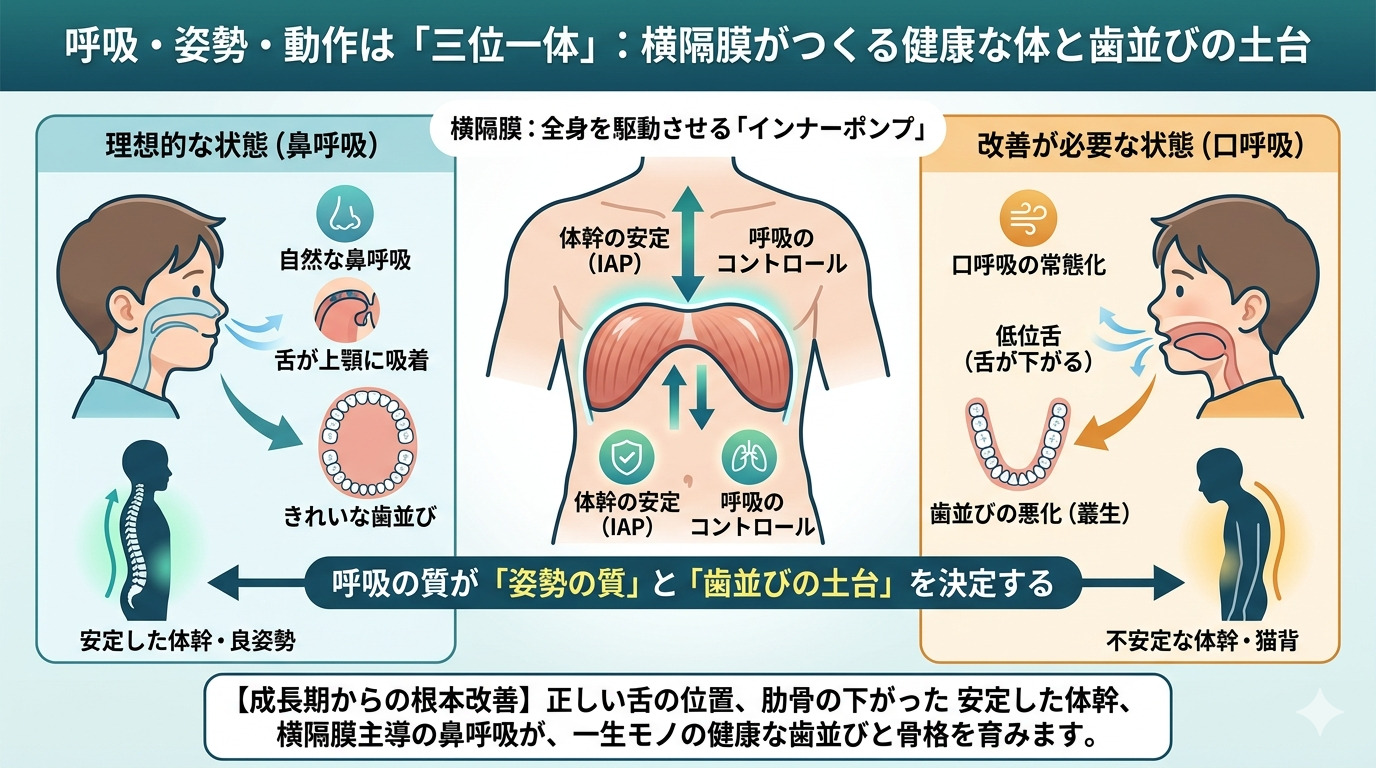

1. 横隔膜:全身を駆動させる「インナーポンプ」の真実

私たちの身体の中には、胸腔と腹腔を隔てるドーム状の筋肉、

横隔膜という名の「生命のエンジン」が眠っています。

その役割は、単に肺に空気を送り込むことだけではありません。

▶️体幹の安定を司る「IAP(腹腔内圧)」の制御塔

正しく深い息を吸う際、横隔膜は力強く下降します。

するとお腹の中に「腹圧」が高まり、

背骨を内側から支える「天然のコルセット」が機能します。

これが、凛とした美しい姿勢の正体です。

▶️現代の子を蝕む「リブフレア」の危機

しかし現代、多くの子どもたちが、

肋骨がパカッと浮いた「リブフレア」という状態にあります。

肋骨が閉じない(リブダウンできない)と、

横隔膜は理想的なドーム形状に戻れず、ポンプ機能が著しく低下します。

その結果、浅い胸式呼吸を余儀なくされ、

身体は常に緊張モード(交感神経優位)に。

「落ち着きがない」「疲れやすい」といったお子さまのサインは、

実は「呼吸の乱れ」が原因かもしれません。

2. 舌は、神様がくれた「世界にひとつの矯正装置」

上顎を押し広げ、理想的な歯並びを作るエネルギーは、

外側(装置)からではなく、内側から生まれます。

その鍵を握るのが、「鼻呼吸と舌」の密接な関係です。

鼻呼吸が確立されているとき、

舌は上顎の裏側(スポット)にぴったりと吸着しています。

1日2万回、呼吸をするたびに

舌の強力な筋肉が上顎を内側から外側へと押し広げます。

この持続的な圧力が、

歯が綺麗に並ぶための「U字型の魔法のアーチ(歯槽骨)」を作り上げるのです。

「口呼吸」という沈黙の代償

もし、口呼吸が常態化し、舌が下に落ちる「低位舌」になってしまったら。

上顎には舌の圧力がかからなくなり、

逆に頬の筋肉による「外圧」だけが勝ってしまいます。

その結果、上顎は狭くV字型に歪み、

歯たちは居場所を失って重なり合い、

アデノイド顔貌(お口ぽかんの顔立ち)の原因となります。

歯並びが悪くなるのは、歯が悪いのではなく、

歯を支える「骨格の成長」が呼吸によって阻害されているからなのです。